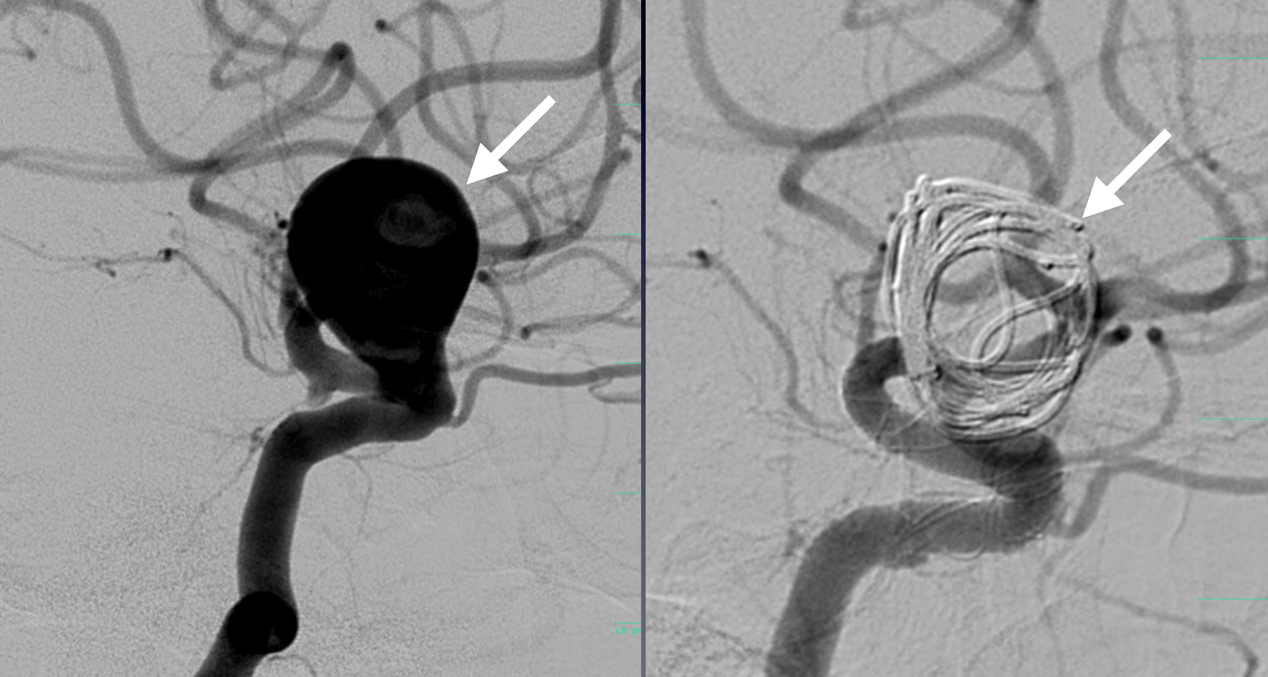

Το ανεύρυσμα της ασθενούς αντιμετωπίστηκε άμεσα με επιτυχή εμβολισμό από την Ομάδα Εμβολισμών του νοσοκομείου. Αυτή η ελάχιστα επεμβατική πράξη περιλαμβάνει την πλοήγηση καθετήρων μέσω του αγγειακού συστήματος στο σημείο του ανευρύσματος και την τοποθέτηση σπειραμάτων ή στεντ, για την αποτροπή της ροής του αίματος στο ανεύρυσμα, αποκλείοντάς το αποτελεσματικά.

Τα εγκεφαλικά ανευρύσματα και οι αρτηριοφλεβικές δυσπλασίες αποτελούν από τις πιο σοβαρές και περίπλοκες νευρολογικές καταστάσεις που μπορούν να προκαλέσουν απειλητική για τη ζωή εγκεφαλική αιμορραγία και απαιτούν ειδική θεραπεία. Το νέο Κέντρο προσφέρει ενδοαγγειακές θεραπείες, μία μέθοδο λιγότερο επεμβατική από την παραδοσιακή χειρουργική επέμβαση η οποία συχνά μπορεί να οδηγήσει σε ταχεία ανάρρωση.

«Περιλαμβάνει μια μικρή τομή, συνήθως στη βουβωνική χώρα, και τη χρήση μικρών καθετήρων που φτάνουν στον εγκέφαλο μέσω των αγγείων του σώματος. Εδώ, οι ιατροί μπορούν να αντιμετωπίσουν την πάθηση με διάφορους τρόπους, όπως με σπειράματα, τοποθέτηση στεντ ή χρησιμοποιώντας ειδική ιατρική «κόλλα», εξηγεί η κα Πολίτη.

Μεγάλο ανεύρυσμα εγκεφάλου πριν και μετά τον Εμβολισμό